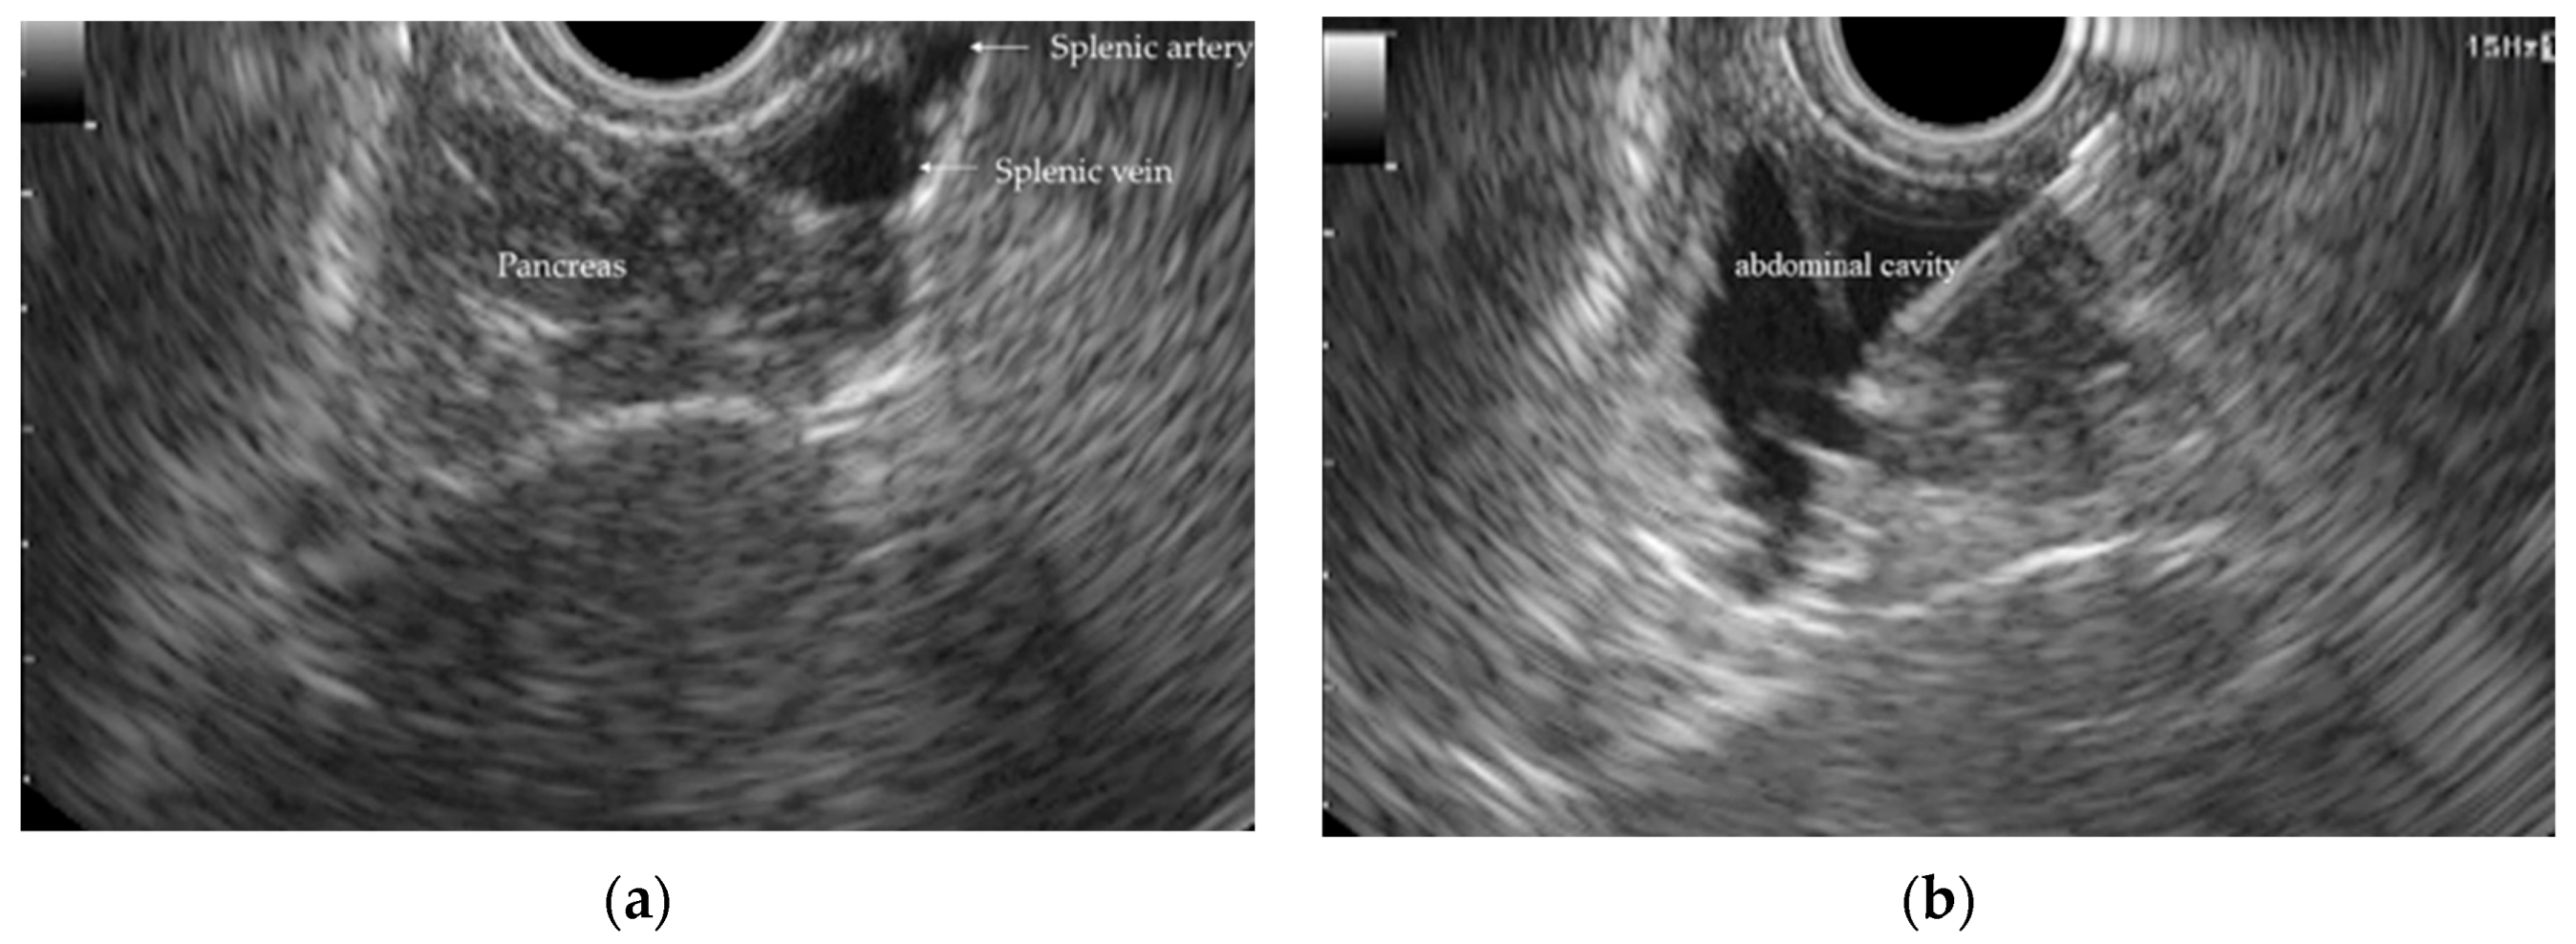

- After inserting the endoscope into the stomach, the pancreas was first visualized in the ultrasound mode. Although the porcine pancreas is thinner and more technically difficult to visualize compared with that of humans, placing the probe against the posterior gastric wall allowed for the identification of the aorta and the celiac artery, as well as the splenic artery and splenic vein. Because, as in humans, the porcine pancreas lies along the course of the splenic artery and vein, these vessels served as useful landmarks for its visualization. The omental bursa is located between the stomach and the pancreas (Figure 2).

- Immediately after detecting the omental bursa located between the stomach and pancreas from the EUS image, under negative pressure, the normal saline solution in the syringe was drawn into the abdominal cavity (Figure 2a).

- Approximately 100 mL of normal saline solution was injected into the peritoneal cavity to insert the guide wire in the abdominal cavity (Figure 2b).